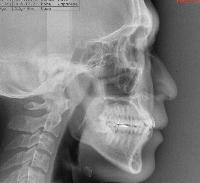

ステップ3. レントゲン (パノラマ,セファロ)撮影 口腔内写真撮影

横顔のレントゲン及び実際の横顔のデジタル画像のコンピューターへの入力の後、

あなたの骨格、歯の状態に合わせて、治療を受けた場合の横顔の変化のシュミレーションを行います。

ステップ3. レントゲン(パノラマ、セファロ)撮影・口腔内写真撮影